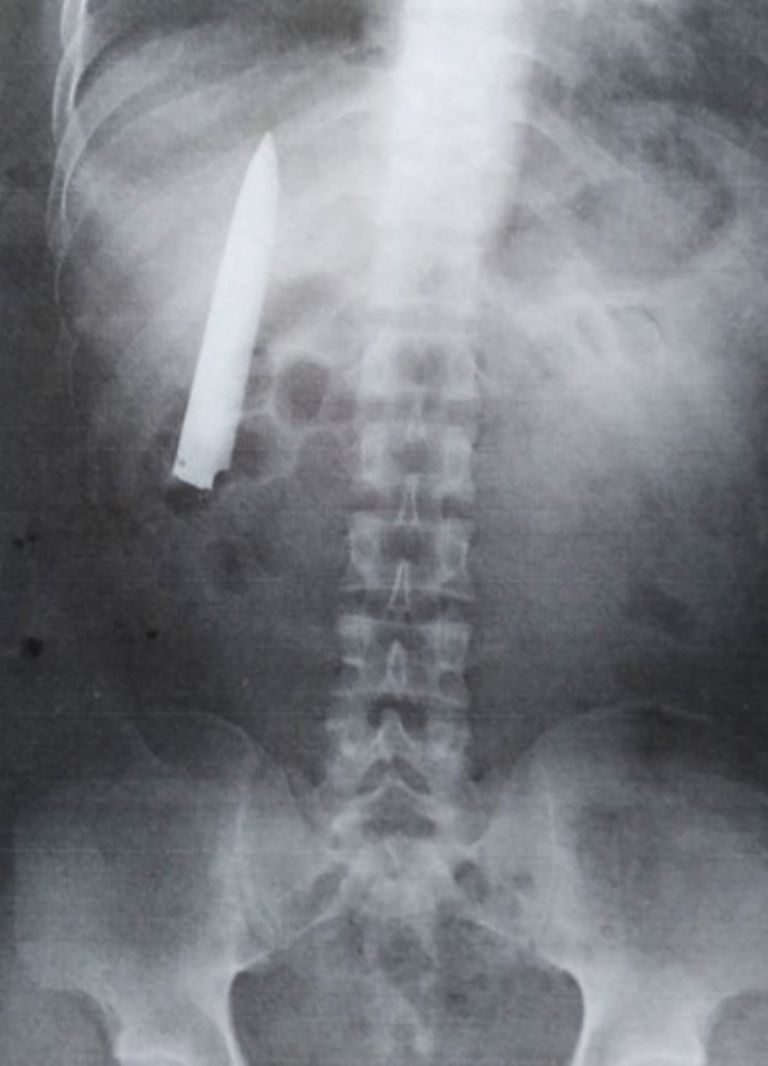

Fue hasta que consiguió un nuevo trabajo que se sometió a una revisión bajo rayos x, ya que era requerimiento protocolario para ingresar. La imagen en blanco y negro lo dejó helado cuando vio la imagen de un cuchillo a mitad de su dorso.

Siempre me pregunté porque sentía dolor en el pecho cuando el clima estaba frío, pero no tenía idea que se debía a que había un cuchillo todavía ahí", explicó.

El joven declaró a medios locales que planea ir al hospital público donde lo saturaron en enero del año pasado para que le retiren la navaja que puede verse cerca de su pulmón. Además, aclaró que no tomará medidas legales en contra del personal médico.